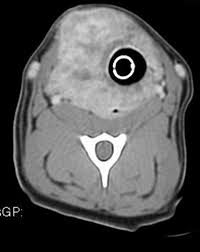

Thyroid Cancer In Dogs Petcure Oncology from petcureoncology.com I'm experiencing this with one of my dogs, a ten year old terrier, right on the heels of losing my other terrier to cancer. Three trials have shown that patients taking psk have fewer chances of the cancer returning; Most of these dogs live at home with their owners and make routine visits to cancer facilities. Dogs that have had massive liver tumors removed have a good prognosis, and may live for years past the operation. On average, how long does it take thyroid cancer to develop in the body? answered by dr. Most thyroid gland tumors do not affect thyroid hormone levels. An idea is obtainable only from the type of cancers, like all ailments, do not follow a particular course. It may also lead to spay incontinence.